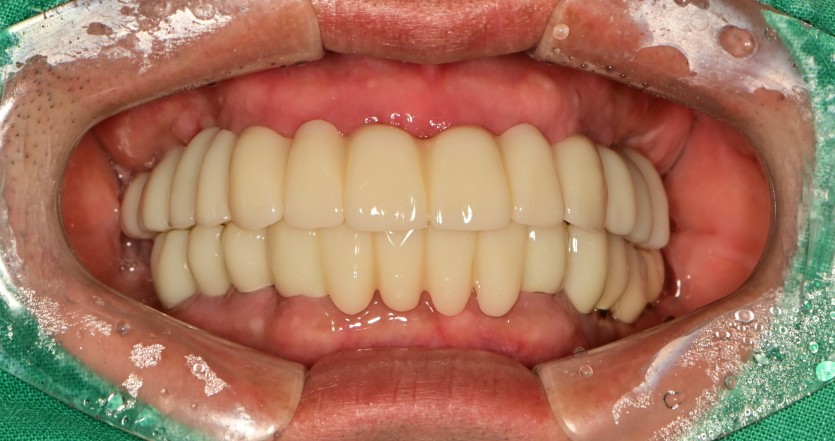

만 41세 전체 임플란트 증례

전체 임플란트 증례입니다.

16개의 임플란트로 완성하였습니다.